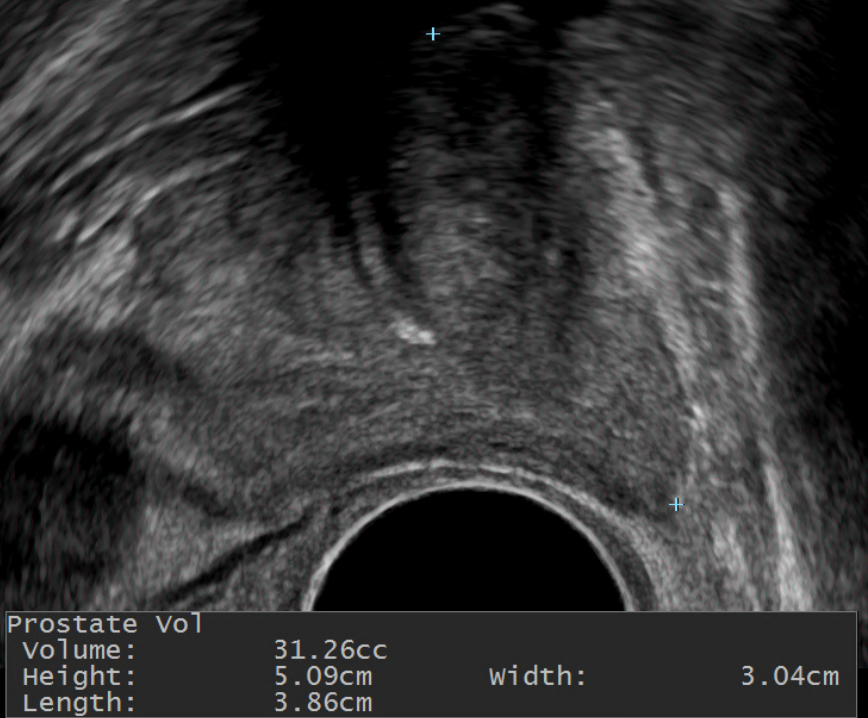

전립선 비대증은 위에서 언급한 증상이 있으면 의심하게 됩니다. 보통은 증상과 관련된 설문지를 통해 정도를 파악해 볼 수 있고, 항문을 통해 검사하는 전립선 초음파는 전립선의 크기를 측정하는데 도움이 됩니다. 혹은 항문으로 손가락을 넣어 전립선을 만져서 크기를 가늠해 보는 직장수지검사를 할 수도 있습니다.